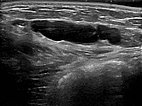

Umschriebene, makrozystische Malformation an der Bauchwand im Ultraschall. Beachte die echofreie Flüssigkeit in den mit Lymphe gefüllten, dünnwandigen zystischen Räumen.

Ultraschall der Bauchwand, etwas weiter kaudal. Hier sind die zystischen Anteile der Lymphatischen Malformation kleiner. Die Läsion liegt jedoch weiterhin extraperitoneal.